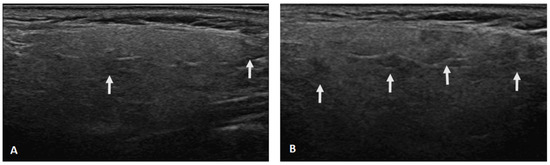

2.2. Salivary Gland Ultrasonography Examination